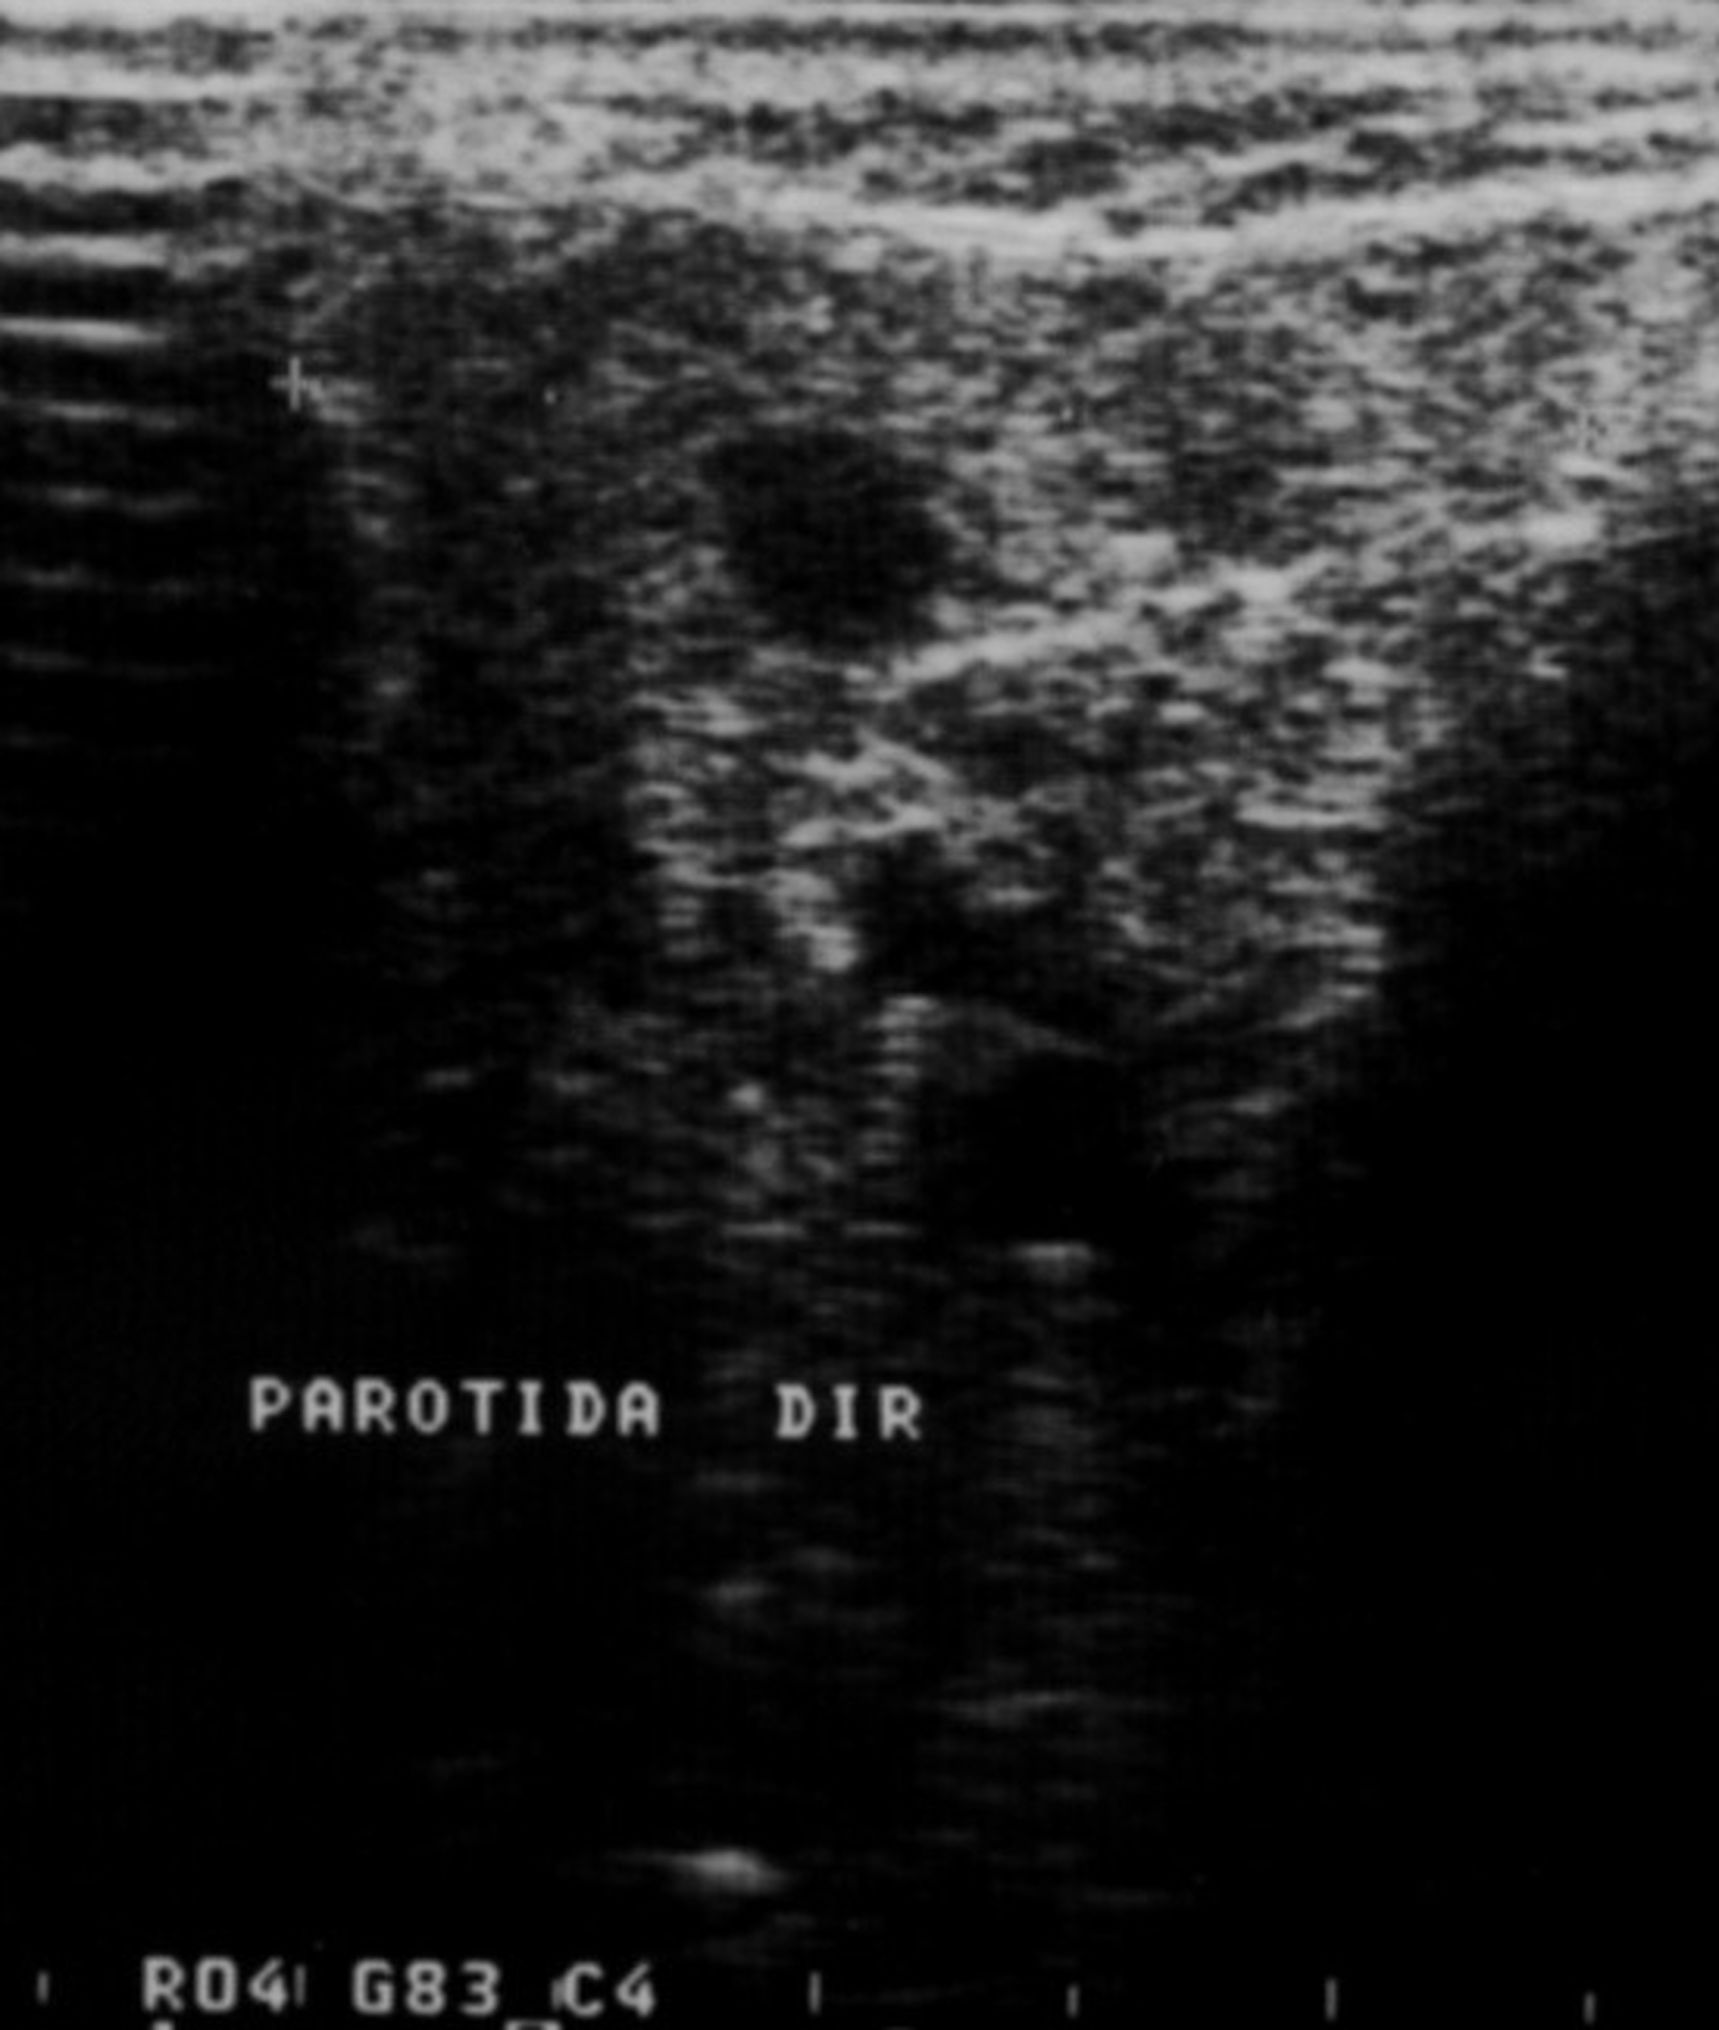

Fig 4. Sonogram of the right parotid gland showing the characteristic parenchymal inhomogenity pattern.

Figure 4

Fig 5. Sonogram in which the right parotid gland shows hypoechoic lesions giving the characteristic nodular pattern.

Figure 5

Imaging analyses, including ultrasonography and sialography, of the parotid glands were performed. Ultrasonographic features of the cervical region did not show any alterations of the submandibular and left parotid glands (Figure 2 through Figure 5). However, the right parotid gland demonstrated an inhomogeneous structure of the gland with scattered, multiple, small, oval, hypoechoic, or anechoic areas, usually well defined, and increased parenchymal blood flow. Sialographic examination of the right parotid gland showed a snowflake-like form and Christmas-tree pattern and evidence of sialoangiectasia without any changes of duct anatomy (Figure 6). Even after the salivary stimulation, the duct system was kept filled by the contrast fluid that again highlighted the sialectatic changes (Figure 7).